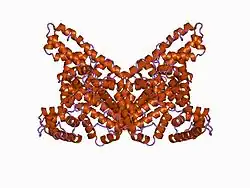

| |

| Structure of albumin | |

The liver produces albumin and then secretes into the bloodstream, where it is then distributed into tissues across the body. In the liver, the liver synthesizes albumin as pre-proalbumin, converts it first into proalbumin and then albumin in hepatocytes, and releases it into the blood.[7] The body synthesizes albumin at a rate of 10 to 15 grams per day. In the presence of hypoalbuminemia, the liver can increase production by as much as four times the baseline production rate.[8] Once released, albumin distributes itself between the intravascular space (40%) in blood vessels, and extravascular spaces (60%) within the body's different tissues. In the blood plasma, albumin makes up 55 to 60% of total plasma protein by mass, with globulins making up a large part of the rest. In hypoalbuminemia, the amount of albumin in the intravascular space or blood plasma is what is being measured, meaning that abnormal distribution within the two compartments may contribute to a relative hypoalbuminemia in the bloodstream with a normal level in the whole body.[3]

Once released into the body, albumin performs a number of functions that can be negatively affected by the reduced levels seen in hypoalbuminemia. These functions include regulation of colloid osmotic pressure or protein concentration within the blood plasma, transport of free fatty acids and other molecules to the liver (unconjugated bilirubin, metals, ions) for storage or utilization, binding of drugs and alteration of pharmacokinetics (half-life, biological activity levels, metabolism), buffering plasma pH, scavenging reactive oxygen species to avoid inflammation and associated damage, functioning as a reservoir of nitric oxide for the regulation of blood pressure, and prevention of coagulation and platelet aggregation in an action similar to the commonly used anticoagulant heparin. It also inhibits inflammatory mediators such as TNF-α and complement 5a (C5a) to reduce the overall inflammatory response.[7]

A number of hormones (e.g. thyroxine, cortisol, testosterone), drugs, and other molecules are bound to albumin in the bloodstream and must be released from albumin before becoming biologically active. For example, calcium binds to albumin; in hypoalbuminemia, there is an increased amount of free ionized calcium, its biologically active form. In the presence of hypoalbuminemia, these functions are differentially affected, and the mechanisms by which they affect disease outcomes remains an area of active debate.[3]